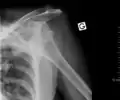

Anterior dislocation of the right shoulder. AP X ray

Anterior dislocation of the right shoulder. Y view X ray.